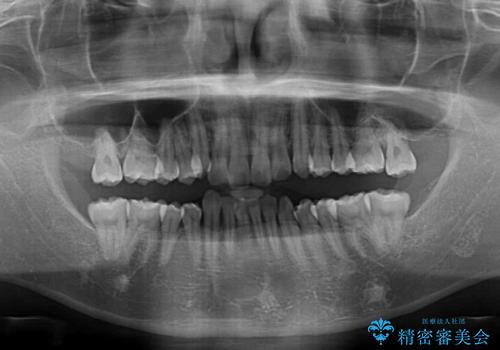

左右ともに奥歯の咬み合わせに問題があり、上顎臼歯が前方位にある状態で、結果として上顎前歯全体が前方位かつ叢生になっていました。

また、左右ともに上顎最後臼歯が頬側に転移していたため、補助装置を用いて舌側に移動をさせながら、上顎前歯を引っ込むように移動させることとしました。

口元の突出感を解消させるため上顎左右第一小臼歯2本を抜歯して、ワイヤー装置にて矯正治療を行うこととしました。